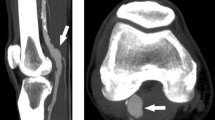

A 78-year old man (Patient 1) with PAA in the left leg was successfully treated with two Viabahn devices (W.L. Gore & Associates, Flagstaff, AZ, USA) sized 9 mm \(\times \)150 mm (proximal stent) and 7 mm \(\times \)150 mm (distal stent). At 12 months follow-up, post-operative CT showed partial stent thrombosis in the transition zone between the two partially overlapped devices. The second enrolled patient (Patient 2) was a 68 year-old man treated in the left leg for PAA with two Viabahn devices sized 10 mm\(\times \)100 mm (proximal stent) and 9 mm \(\times \)150 mm (distal stent). In this patient, intra-stent thrombosis was revealed already by 1 month follow-up CT scan.

Postoperative CT images were anonymized and transferred to a workstation for image processing. Segmentation of the vessel lumen from the femoral artery bifurcation to the popliteal artery bifurcation, intra-stent thrombosis, leg bones, and the implanted stent-graft(s) was performed by means of Vascular Modeling ToolKit (VMTK) libraries [19]. A surrogate pre-thrombotic model of the lumen was derived by virtually removing the thrombosis during the image segmentation in order to correlate hemodynamic with thrombosis onset. Rigid registration of bent-leg structures on their corresponding straight counterparts was automatically performed by means of the Iterative Closest Point algorithm implemented in VMTK. Centerline vessel was automatically extracted, smoothed and resampled by 0.5 mm by means of VMTK libraries [20]. Centerline tortuosity was then computed: it represents an important factor in different cardiovascular diseases, i.e., atherosclerosis, abdominal aortic aneurysm, and, in particular, in thrombus initiation [21]. Tortuosity (T) is measured as follows: given the centerline length (L) and the shortest distance between the two centerline endpoints (ED), \(T = L/ED-\)1; therefore, with this definition, the tortuosity of a straight line is 0.

Femoro-popliteal artery and three zoom views of the lumen (rotating clockwise) of both the patients in straight-leg configuration: the area where the thrombosis is localized is highlighted by a black box. Moreover, blood flow helicity is represented: in blue the flow with negative LNH and in red the flow with positive LNH